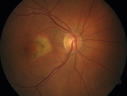

Pattern Dystrophy - Adult Vitellifrom (Best)448 views71 year old female - lesions nasal to the fovea in both eyes. (20/40 OU)00000

Pattern Dystrophy - Adult Vitellifrom (Best)408 views71 year old female - lesions nasal to the fovea in both eyes. (20/40 OU)00000

Pattern Dystrophy - Adult Vitellifrom (Best)436 views71 year old female - lesions nasal to the fovea in both eyes. (20/40 OU)00000

Pattern Dystrophy - Adult Vitellifrom (Best)484 views71 year old female - lesions nasal to the fovea in both eyes. (20/40 OU)00000